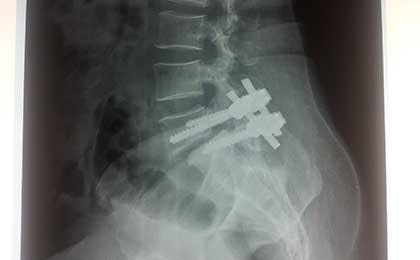

POST OP XRAY LAT

post op x ray lat 1

post op L5 S1 FIXATION

post op dorsolumbar fixation x ray